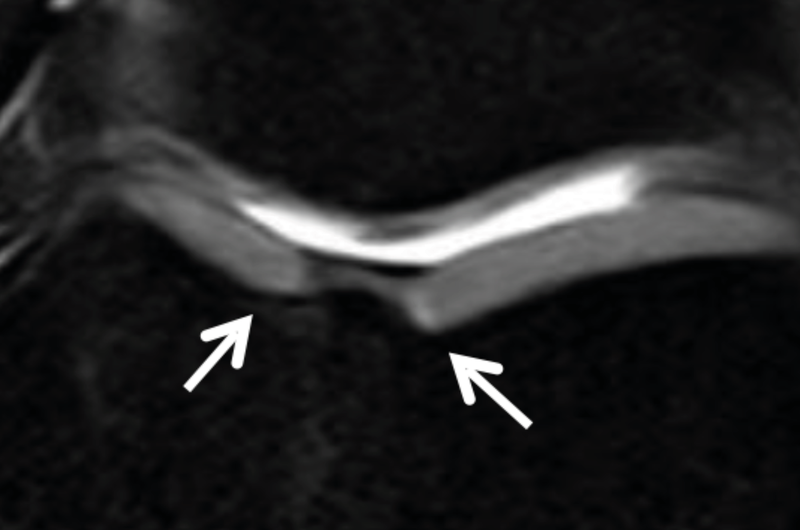

Radiographic analysis requires a weight-bearing full leg and lateral knee joint x-ray and a standard axial image of the patella. In addition, the extent of the narrowing of the joint space in the affected joint compartment should be assessed with a Rosenberg view (p.a. radiograph with weight-bearing and 45 degrees of flexion) or stress x-rays with varus/valgus stress. Since large numbers of unicondylar knee replacements are performed in our hospital, stress radiographs are standard for any unicompartmental OA requiring surgical treatment. The extent of the joint collapse and the stability of the joint can be diagnosed by these radiographs (Fig. 6, 7).

The deformity analysis of the full radiograph with the relevant measurements according to Dror-Paley (weight bearing line, mechanical axis, LDFA and MPTA) as well as the assessment of the joint line obliquity (JLO) and joint line convergence angle (JLCA) are of central importance. The planning for realignment osteotomy is standardized with an appropriate digital planning tool (e.g. mediCAD®). (Fig. 8)